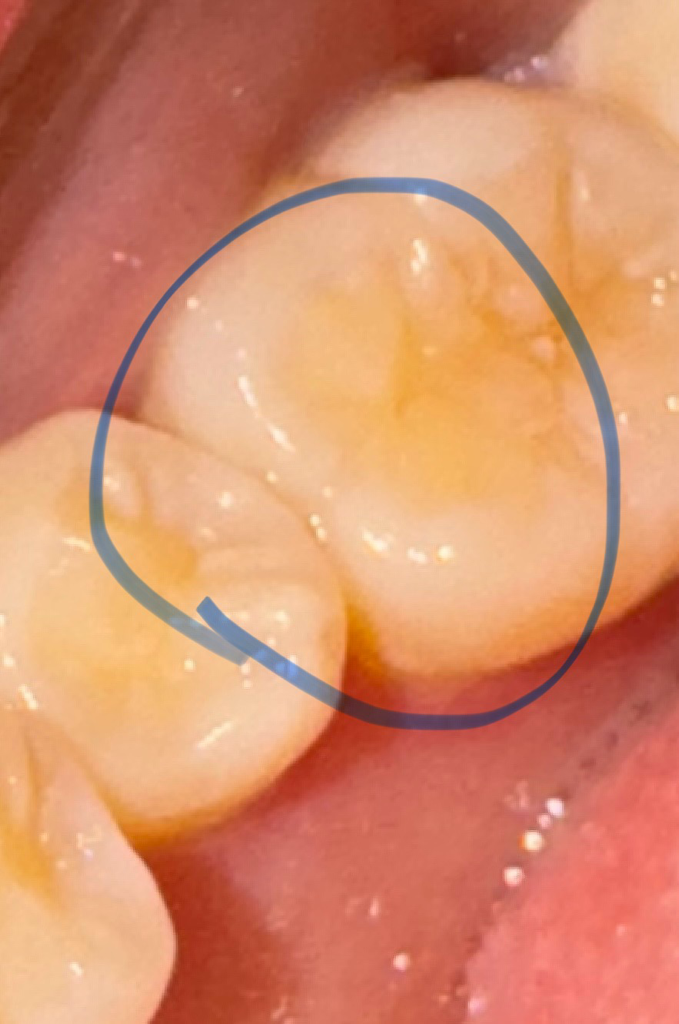

사진 속 부위가 약간 시린듯한데 이유를 모르겠어요

정확하진 않지만 동그라미 친 부분 쪽이 시린듯 안 시린듯 느낌이 가끔 이상해요

• 1번 째 사진

사진으로 봤을 때는 치아에 큰 문제가 있어 보이진 않습니다. 이상이 없음에도 치아에 불편감이 있다면 치아에 너무 과도한 힘이 가해지고 있지 않은지 확인해 보는 것이 좋습니다.

사진상으로는 특별히 문제점이 보이진 않습니다. 지켜보시고 증상이 계속되면 치과 가보시는 게 좋겠습니다.

사진상으로는 크게 문제가 잇어 보이진 않습니다. 잇몸이 안좋아서 그럴수도 잇으니 치과에 가셔서 잇몸치료를 먼저 받아보세요.

사진상으로는 교합면 약간의 마모만 보일뿐 큰 병적인 상태는 없어보입니다

치과에서 불소도포 내지는 지각과민처치(보호막 코팅)를 해보시기 바랍니다

현재 사진상으로는 이상이 보이지 않으며, 시린원인은 다양하며, 해당잇몸에 치석이 있어 잇몸에 염증을 유발할가능성도 있습니다. 빠른시일내에 치과에 방문하여 상태를 확인하고 치료를 받길 권합니다.